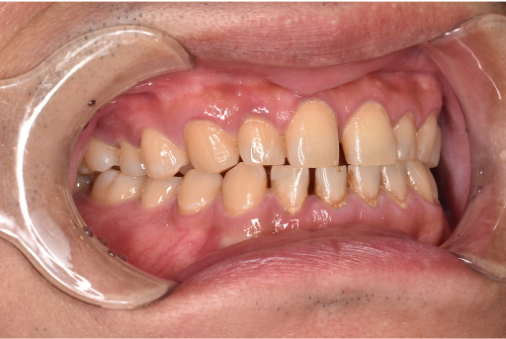

general 30代男性「タバコのヤニが気になる」縁上歯石・着色を除去し、その後歯周治療を行った症例

治療前

| カウンセリング・診断結果 | こちらの患者様は1日20本ほどタバコを吸われる方で、歯医者は十数年振りとのことでした。 縁上歯石と全体的に縁下歯石が付着しており、歯ぐきが赤く腫れ炎症しておりました。前歯の歯頸部や裏側に着色も認められました。歯周病検査により中等度の歯周炎が認められたため歯周治療も必要でした。 |